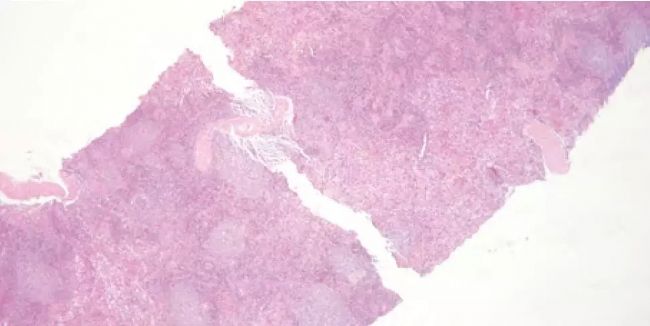

B. 鏡下可見(jiàn)從大的脂肪樣本中選取的皮下組織脫水不足,纖維脂

肪組織浸蠟不充分,核界變得支離破碎。